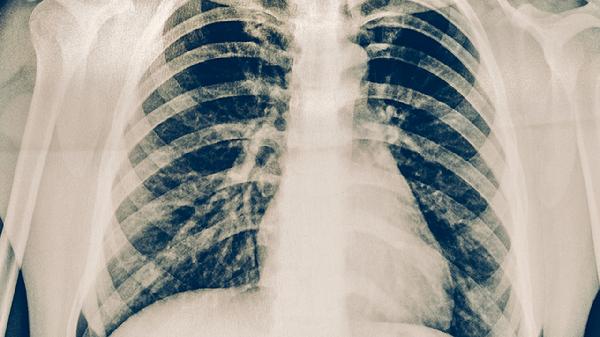

肺结核复发患者应保持充足营养,每日摄入优质蛋白如鸡蛋、鱼肉等,补充维生素A、D和锌等微量元素。注意隔离居住,咳嗽时用纸巾遮掩口鼻,痰液需消毒处理。建议家属进行结核菌素试验筛查,出现低热、盗汗、咳嗽等症状及时就医。完成治疗后仍需随访2年,每3-6个月复查胸片,确保无再次复发。